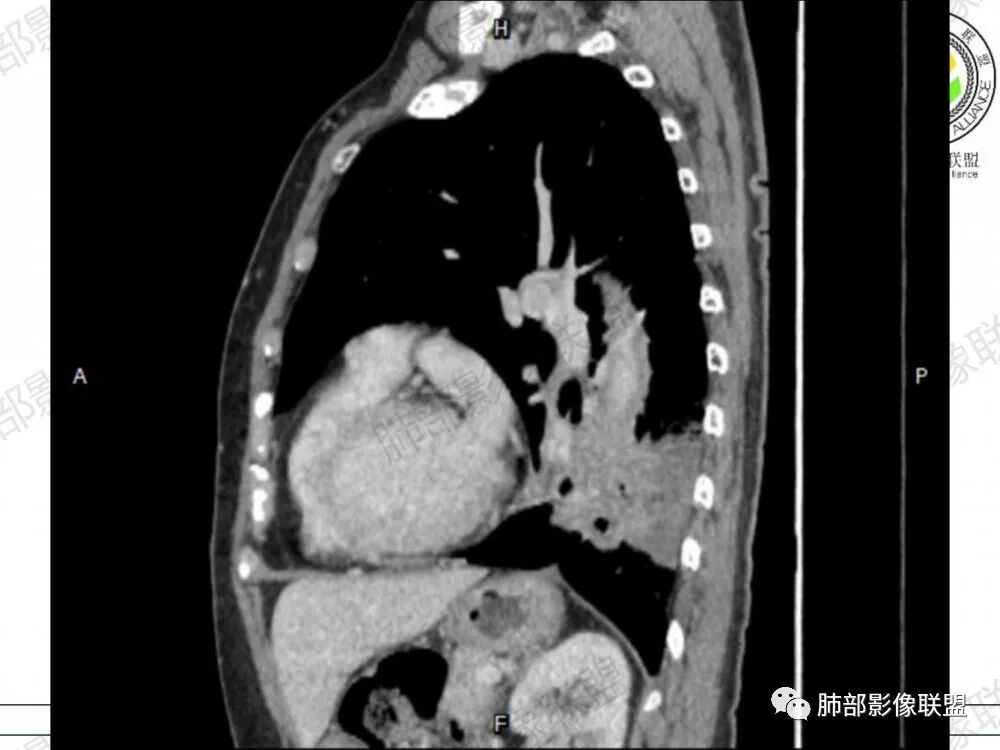

晨读病例,老年人男性 左肺下叶病灶,实性病变加上边界清晰的磨玻璃影,实性病变可见明显的膨胀性生长,增强实性部分可见血管照影征,考虑腺癌,粘液腺癌可能。

左肺下叶胸膜下混合磨玻璃影,磨玻璃边界清晰,支气管进入后堵塞,增强轻中度强化,无明显坏死空洞。

空腔+铺路石征+边界清楚GGO+病灶内血管局部扭曲+强化不均匀+病史长,指向腺癌,特别是粘液腺癌

晨读:左肺下叶胸膜下实性高密度影,部分伴有网格样增厚,内部可见小空泡,壁光滑,周围伴有磨玻璃影,边界清,近端可见支气管穿行,远端支气管堵塞,胸膜下脂肪间隙可见,病变整体收缩,部分有彭隆,增强后可见血管穿行,强化尚均匀。

左肺下叶实变及磨玻璃影,宽基底与胸膜相远,磨玻璃边界清晰,边缘膨隆,病变内近端支气管堵塞,不均匀强化,可见血管影,考虑腺癌,鉴别结核

胸CT:左下叶胸膜下大片斑片影,长轴沿胸膜分布,实变、GGO混杂,磨玻璃边界清晰,粘液密度,小叶内间隔增厚,支气管进入后堵塞(枯枝),增强轻中度强化,血管造影征。常规考虑:肺腺癌?淋巴瘤?鉴别不典型病原体感染。

周围GGO,呈碎石路征,边界清楚

主体病灶

2、影像表现:无肺气肿背景,病变定位于左肺下叶背内侧基底段,病灶呈不规则团块影,靠近胸膜侧,其内密度不均匀,内见空洞、实变及磨玻璃影,磨玻璃影呈碎石路征,边界清楚,实性肿块边界膨隆,其内见空洞。空洞周围比较实。病灶较大的支气管通畅,细小的支气管成“枯枝征”。无胸膜增厚及胸膜腔积液,增强扫描呈中度强化,见血管造影征。